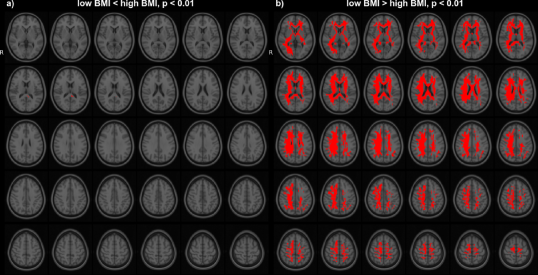

In the HCP dataset, ODFs correlate strongly with the demographic variable BMI. As expected, the ODFs negatively correlate (Fig. 7b) with BMI, indicating a loss of anisotropy with increasing BMI (Fig. 5a,b). This result is consistent with the well-established negative association between global white matter integrity and physical obesity (Mueller et al., 2011; Stanek et al., 2011; Verstynen et al., 2012; Gianaros et al., 2013; Verstynen et al., 2013). The fiber directions (Fig. 8a,b) identified from can be used to perform tractography (Fig. 8c,d). Resulting tracts (Fig. 8c,d) show a pronounced loss of anisotropy in the corticospinal tracts, the optic radiations and the right superior longitudinal fasciculus. These results are corroborated by the existing methods TBSS (Fig. 9a,b, S2a,b), Connectivity-based fixel enhancement (Fig. 9c,d, S2c,d) and local connectometry (Fig. 9e,f, S3a,b). The volume of positive findings of correlation with BMI is largest when using the full ODF information with the ODF approach (Fig. 9). In addition, in a test of specificity, no voxels are found to correlate with randomly permuted BMI (Fig. S4).

Several methods exist to analyze populations of diffusion MRI datasets, typically working on a reduced dimensionality subset of the diffusion data. TBSS (Jbabdi et al., 2010), limiting the analysis to a projection to a tract skeleton, succeeds in identifying the tracts most significantly correlated with BMI (analysis of FA, Fig. 9a,b, S2a,b) but misses the full extent of the correlations. The Connectivity-based fixel enhancement (Raffelt et al., 2015) and Connectometry (Yeh et al., 2016) approaches do include more of the available information and hence perform better than the TBSS method (Fig. 9c,d, S2c,d (Fixel enhancement) and 9e,f, S3a,b (Connectometry) vs 9a,b, S2a,b (TBSS)).

None of the above methods however capitalizes on the full ODF information. This in contrast to the approach presented in this paper. The ODF approach indeed identifies a larger volume of significant findings (227 cm3) than the existing methods tested here (TBSS 17 cm3, Connectivity-based fixel enhancement 15 cm3 and Connectometry 212 cm3, Fig. 9b,d,f,h,j). That is, by analyzing the full ODF information and not reducing the dimensionality of the diffusion data, as is commonly done, the ODF approach is able to pick up on smaller significant changes, better grasping the full extent of the significant findings. Limitations on computational power and diffusion acquisitions (e.g. DTI) which inspired the data reduction of older methods no longer exist. It is hence advisable to maximize the amount of information included in the analysis as in the approach presented here.